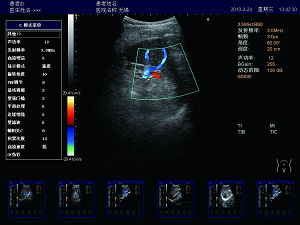

精確血流成像

智能識別血流運動和組織運動,使血流更充盈,組

織邊界更清晰。

肝臟 脾臟 多普勒血流

高效的多譜勒技術

多普勒幀相關 血流圖像更平滑更清晰。

多普勒快速優化 對于危重病人,兒童可以在短時間內獲得最佳的血流成像。

壁濾波器 增強血流邊緣清晰度,產生精準的發射波形,達到最佳匹配效果,提高全聲場的回波質量。